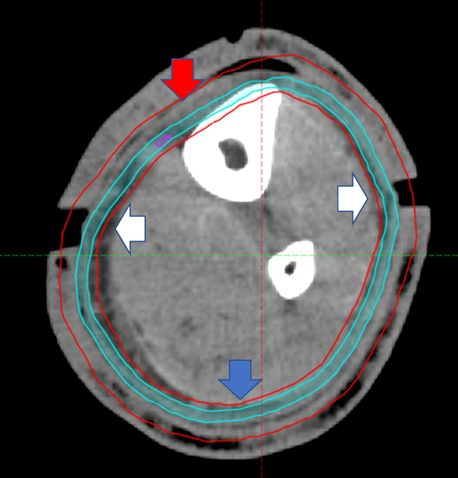

He represented for a planned restart at 16 days post the 10th fraction and had no pain. The legs were clinically swollen, and this was confirmed on tape measurement – see table 2. The RT staff noted that the bolus was not fitting as it should and surmised that this could be an early sign of lymphoedema. He had another fraction, and Cone Beam CT (CBCT) showed an increased gap in the joints of the 3DPB. A repeat CT scan was done, and on fusing the original contours, the CTV was not covering some of the anterior epidermis, a geographic miss. The posterior surface was satisfactory because presumably the gravity of the leg weight was keeping the posterior part of the CTV and PTV contours within the limb at their original position. (See figure 6). The volume changes were recorded – see table 2.

Figure 6 Rescan of Right leg at 2 weeks following completion of 18Gy in 10 fractions at 15cm proximal to medial malleolus. Compare with Figure 3A. Note swelling demonstrated by increased bolus joint width as shown by white arrows. Red arrow shows that the CTV is not covering the epidermis anteriorly, therefore causing a geographic miss. The PTV is covering more depth into the leg, especially the vascular dermis and subcutis which may set up a positive feedback loop, worsening the tendency to acute lymphoedema. The blue arrows show that posteriorly the CTV still covers the epidermis, presumably because of the weight of leg with gravity as he was treated in the supine position.